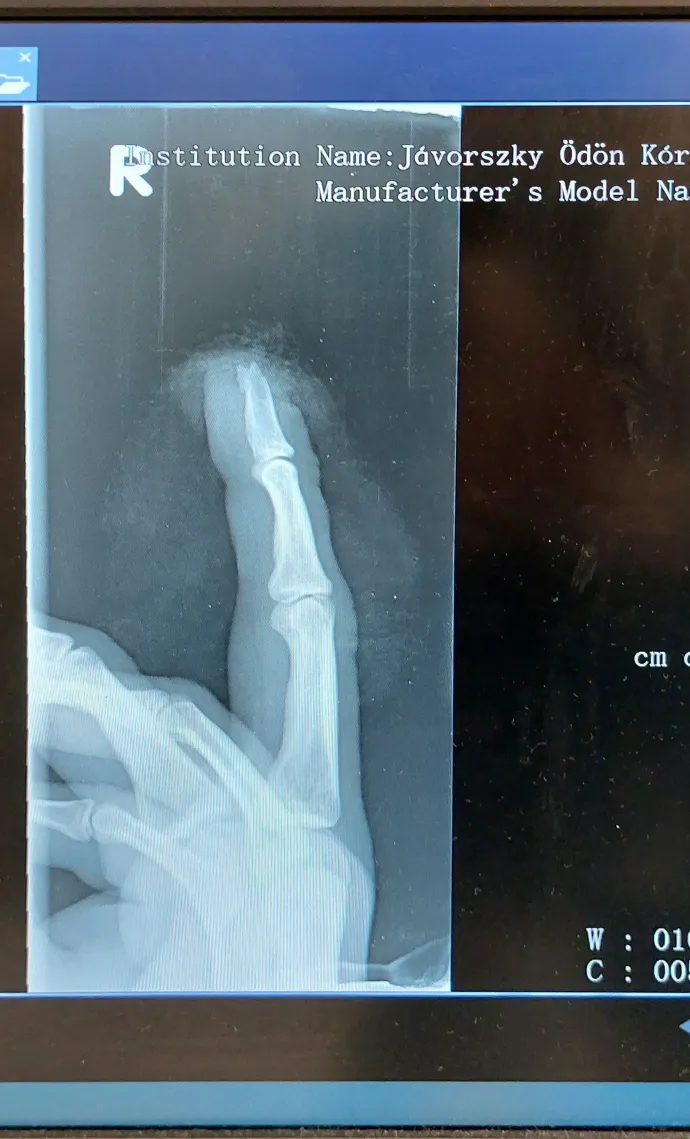

– mesélte Ádám. Ahogy levette a kesztyűt, észrevette, hogy a jobb keze középső ujjáról hiányzik az ujja vége. A meginduló tálca alsó, és az alatta lévő tálca felső pereme alá szorult ugyanis az ujja, így lecsípődött az ujjvég csont nélküli szakasza.

Ádám leült a földre, míg kollégái elszorították a vérzést, és kihívták a gyár belsős mentőszolgálatát. Miután megérkeztek, Ádámot a gyár bejáratánál található orvosi helyiségbe szállították. Az ambuláns lap szerint ott bekötözték az ujját, és alkoholtesztet csináltattak vele. Hányáscsillapítót és egy opioidalapú fájdalomcsillapítót adtak neki, majd továbbirányították a Váci Jávorszky Ödön Kórház traumatológiai osztályára.

Ádám visszaért a csarnokba, ahol a munkavédelmi dolgozók kikérdezték a történtekről. Miután elengedték, a gyárból rögtön a Váci Jávorszky Ödön Kórházba ment. „Akkor tudtam meg, hogy nagyobb a baj, mint gondoltam, amikor bementem a váci sürgősségire. Ez nem egy gyors dolog, van, aki órákat ül ott. Engem öt perc után behívtak” – mondta Ádám.

Miután az orvos megröntgenezte a kezét, kiderült, hogy a balesetben az ujjában lévő csontból is letört egy darab, ami miatt amputálni kellett az utolsó ujjperc felét. Az ambuláns lap szerint az orvosok több vizsgálatot is felírtak neki a következő napokra, és úgy számoltak, hogy két hét múlva, január 11-én ismét munkaképes lehet.